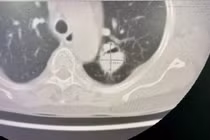

Bệnh viện Đa khoa tỉnh Quảng Ninh vừa thực hiện thành công ca cắt thùy phổi cho bệnh nhân nữ 65 tuổi mắc u nấm phổi phức tạp, chấm dứt tình trạng ho ra máu kéo dài.

Bệnh nhân Đ.T.L., trú tại Hưng Yên, có tiền sử bệnh phổi tắc nghẽn mạn tính, nhập viện trong tình trạng ho nhiều và ho ra máu tái diễn. Kết quả thăm khám, hội chẩn xác định bệnh nhân có u nấm phổi thùy trên phổi trái, nguy cơ chảy máu nặng nên được chỉ định phẫu thuật cắt thùy phổi.